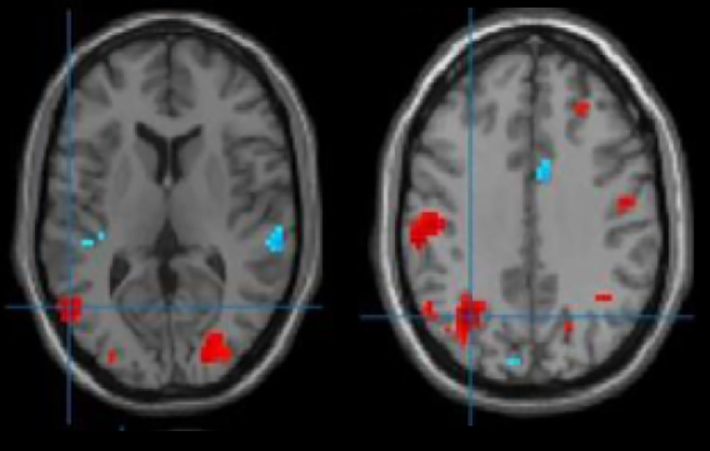

鼠标手的脑部功能核磁示脑部特定功能区出现可塑性变化

我们近2000例腕管综合征的临床研究证实,一侧手术可以缓解双侧;

▶初步研究证实,这一现象与大脑的可塑性改变密切相关。